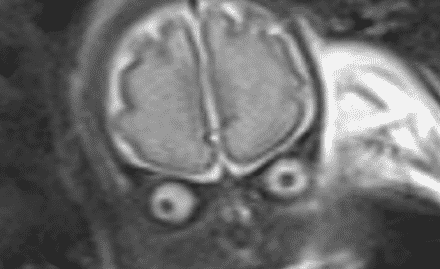

Un gynécologue libanais a publié sur son compte Instagram une photo qui a ému le monde entier. Celle-ci montre un […]